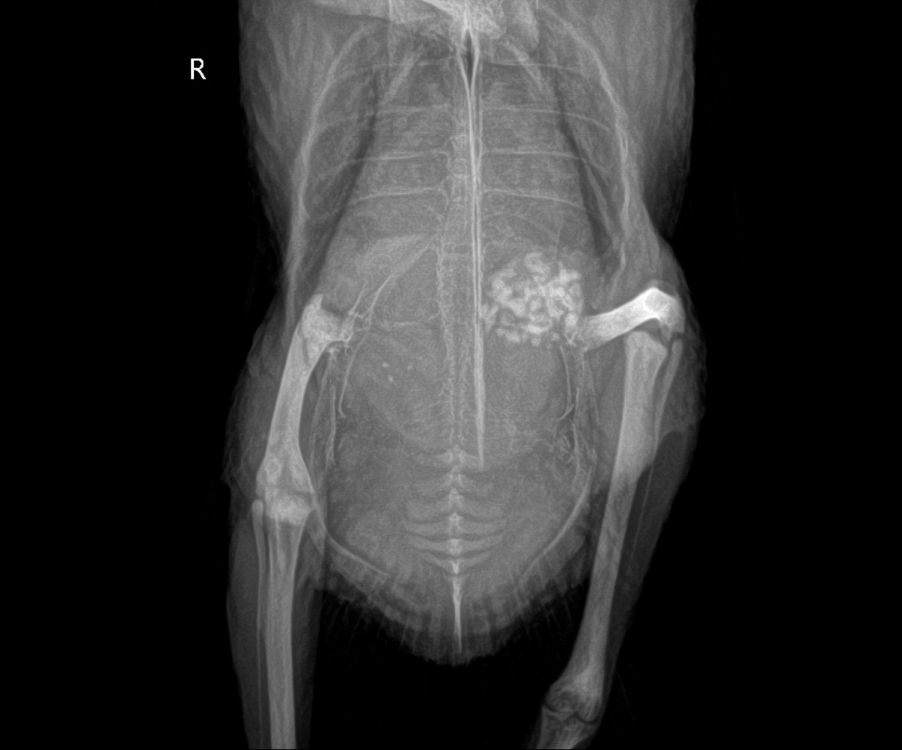

PiratelParrot Опубликовано 12 августа, 2022 Автор #417 Опубликовано 12 августа, 2022 Неделя наблюдений. Помёт гуляет из крайности в крайность ежедневно в течение суток. В одно и то же время. Бесцветность, как было недавно, прошла, но появилась новая фигня. Раннее утро - отличная плотная огромная какаха (сидит в гнезде, копит). Идеально болотная с белоснежными уратами. Не сфотал. Утро - фото 1. Ни капли воды. Выходит вчерашний ужин. После утренней кормёжки начинается фото 2 - жёлтая вода, но ураты при этом белые. До середины дня продолжается этот жёлтый водопад вплоть до исчезновения кала, остаётся просто свободная вода - фото 3. Потом начинаются маленькие вкрапления переваренного и к вечеру помёт снова приходит в норму - фото 4. Почти каждый день в течение этой недели одно и то же (только один раз 2 дня подряд была всегда норма).Кормёжка: вручную перловкой, смесью ячки и капли пшеницы (боюсь её вводить из-за кандиды), немного гороха. Остальное он доедает сам сколько ему нужно (только просом и зелёной гречкой). Зелень пока не даю. На этой кормёжке птиц опять поправился до 349 г. Лекарства: гептрал, карсил, пимафуцин. Состояние: вроде активный, живот отчасти сдулся, но всё равно есть. Горбится по обыкновению уже который месяц. Голос появился только вчера. Стали снова массово опадать мелкие перья (с началом гептрала). Вопрос: от чего льются жёлтые лужи? В мае я тоже давал гептрал, но такого не было. Только на урсосане стало всё желтеть и мы его отменили. Такого вообще никогда с ним не было. Вне яичных обострений.Очень прошу не игнорировать Пишут, что с гептралом шутить нельзя, а я теперь даже не уверен, правильно ли я его даю. Посмотрите еще раз снимки старого рентгена, пожалуйста. Зося говорила, что печень увеличена, а потом сказала, что её плохо видно. У меня сомнения и я не знаю, что делаю не так. И ЕЩЕ. Голубь хрюкал всегда, сколько его знаю. Когда в руки берёшь или вырывается. Еще этот феномен пропадающего раз в месяц голоса. Начавшийся с яйцекладкой в декабре, странно возвращающийся то через пару дней, то через две недели. Зося разглядела на рентгене очаги былого микоплазмоза. Он что, мог сам пройти? Или он там может до сих пор быть? И не связаны ли его хрюки с хронической микоплазмой? Про анализы на эту пакость я спрошу в вет.клиниках (но успеха не жду, скорей всего, откажут). Что делать со всем этим? Прямо сейчас.

PiratelParrot Опубликовано 12 июля, 2024 Автор #427 Опубликовано 12 июля, 2024 Вот что нашёл. В 19.02.2023 в 01:10, Zosia сказал: Это гранулема. Скорее всего- денатурированный белок несформированного яйца или кисты. У меня есть (были) такие пациенты. И кровь связана именно с этим. https://public.fotki.com/Shemlik/aspergillosus/001.html https://public.fotki.com/Shemlik/aspergillosus/13.html https://public.fotki.com/Shemlik/bc6ed/9fa0.html первые два случая- системный микоз (аспергиллез) яичника, препятствовавший нормальному росту фолликула, дававший воспалительный процесс с выпотом фибрина. Потом это все "рождалось"- сносилось как яйцо. Последний случай- просто поликистоз с фибринозом яичника, и рождение атких вот объектов. Первая птица какое-то время жила, потом погибла при попытке родить гранулему более 3 см в поперечнике- смерть от перфорации кишечника и кровопотеря. Втьорая и третья птицы живы по сию пору. Но они=- молоды, в отличие от вашей. И без отягчения вертячкой. Поэтому- то что я вам писала в личке. Плюс кровостанавливающее в/м. Плюс преднизолон, но только после прекращения кровотечения- доза 3 мг/кг в сутки. Прогноз- отрицательный. Птица старая.... А если всё это время "он" не нёсся потому что микоз и воспаление? Отсюда и угнетённое состояние в момент, когда типа надо снестись, и живот вздутый, и ведь с самого начала я грешил на кандиду т.к. флук работал и уменьшал симптомы, так может, он работал не на несуществующую кандиду, а на аспергиллу? Но я прекратил любые антимикотики почти 2 года назад т.к. угробилась его печень, и за это время бывали и тяжёлые моменты, и очень легко проходящие, но организм как-то сам перерабатывал эти белки, а в этот раз уже не смог? И еще это состояние фиговое очень связано с его весом. Он с детства, т.к. сам не ел категорически и питался только моими всыпками в клюв, оказался закормленным и разжиревшим. Как только он не так давно похудел стабильно до 340, а еще лучше до 330+\- г, болячка стала протекать облегченно, я иногда вообще ничего не давал ему в эти моменты. И еще лучше стало на фоне пролеченной от предположительно жирового гепатоза печени (гептрал месяц, гепатовет 1,5 месяца, хофитол и липоевая 15 дней). Но в этот раз опять резкий набор веса (могло такое быть от черешни?) и опять горбатая спина, надутый живот, тяжёлое дыхание, вода вместо помёта, а как вишенка на торте сегодня - вот эта "киста" с кровью. Чё с ним делать... 1 час назад, маленький принц сказал: что с ними случилось? крайне жалко попугаев Очень жалко. У одного, волнистого, какая-то хронь была невыясненная после того, как бабуля дементная накормила его сладкой булкой. Он то сиял здоровьем, пел и играл, то сидел угнетённый с рыжими лужами помёта. Лечил ему и кандиду, и мегабактериоз, и печень. Прожил так 4 года, а после курса чиктоника у него отказали лапы одна за другой и всё. Угас за несколько дней. У второй, лысой кореллы, через 2 недели после чиктоника открылся яйцемёт неудержимый (она и так неслась за 6 лет, но нечасто) и в какой-то момент она резко затошнилась, перестала есть, ни один из наработанных мной методов облегчения состояния не сработал, а от глюконата кальция у неё будто случился инфаркт. Еще и грелку ей сунул в клетку.... что было явно лишним. В общем, быстро умерла, никто не ожидал. Оба ушли почти одновременно. Это было горе.